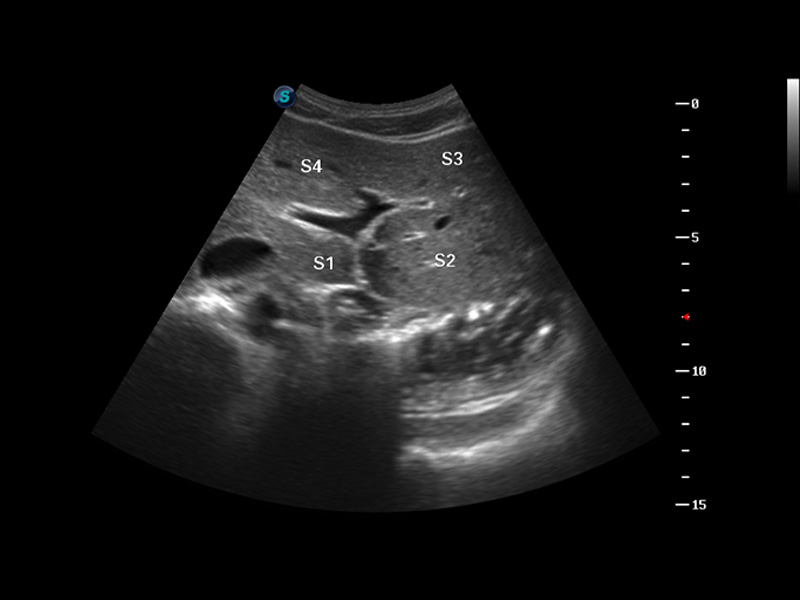

S8 EXP便携式彩色多普勒超声诊断仪是乐玩lewin国际研发的高端全身应用型便携彩超。高通道的VIS平台融合可视化(Visual)、智能化(Intelligent)和人性化(Smart)的特点,配以乐玩lewin国际自主研发生产的探头大家族,使您能够快速、准确的获得病人信息,提高工作效率的同时减轻疲劳。